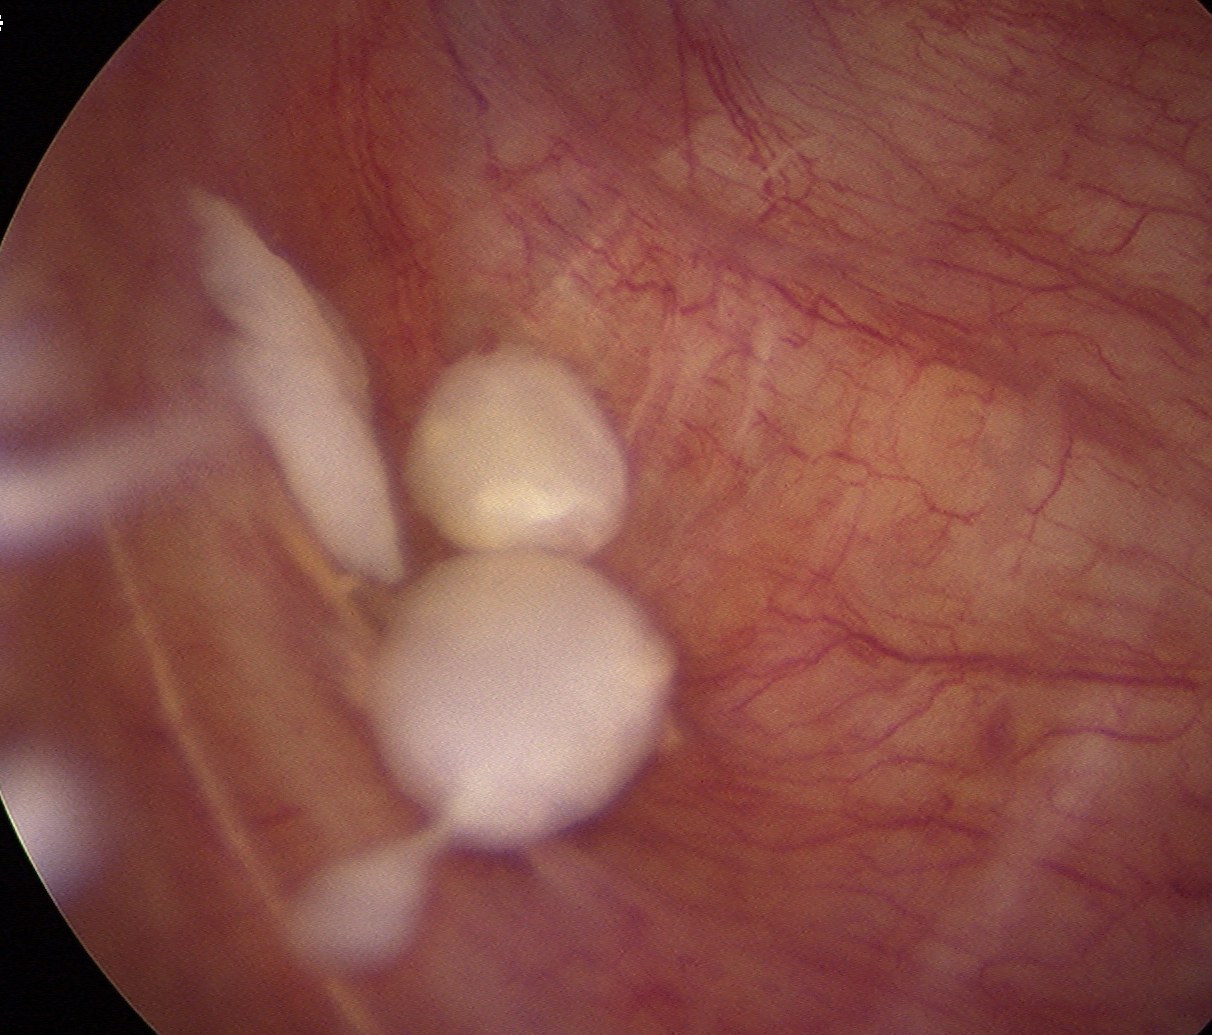

Arthroscopy

Synovial proliferation

- localised or generalised

- can see cartilage growing from synovium

Multiple loose bodies +++